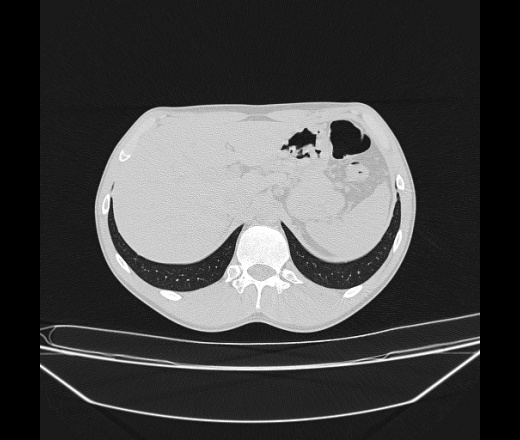

Молодой парень 18 лет, призывник, при прохождении ФЛС на верхушек левого легкого выявили очаги средней интснисвности с нечеткими контурами, тяжи. Сделали бок и томограммы 6-7-8. Везде описывают как очаговый твс. Вижу только перибронхиальный фиброз. Что за изменения в бронхах, указано нижи стрелками, тоже перибронхиальный?

Не стал бы говорить об очагах. Акцентировал бы не на фиброзе, а на тракционных бронхоэктазах. Не обязательно они результат tbc бронхов, но проверить не помешает.

Иван, пациент ведь уже "направлен с ОПТД", так?surprise Возвращайте его назад с заключением о возможном микобактериозе. Остаточные поствоспалительные ( посттуберкулёзные?) в дифряд.Очаговый твс с неясной активностью они уже себе "нарисовали", как я поняла.